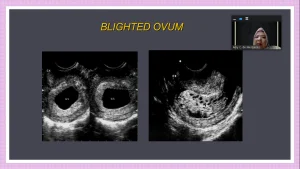

Pembicaraan 1: dr. Amy Cynthia de Meriyenes.

Topik: USG dalam kehamilan